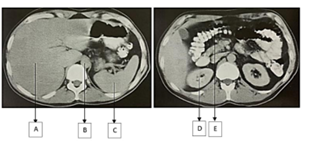

Observe as imagens de tomografia computadorizada:

Considerando os órgãos representados a associação está correta em